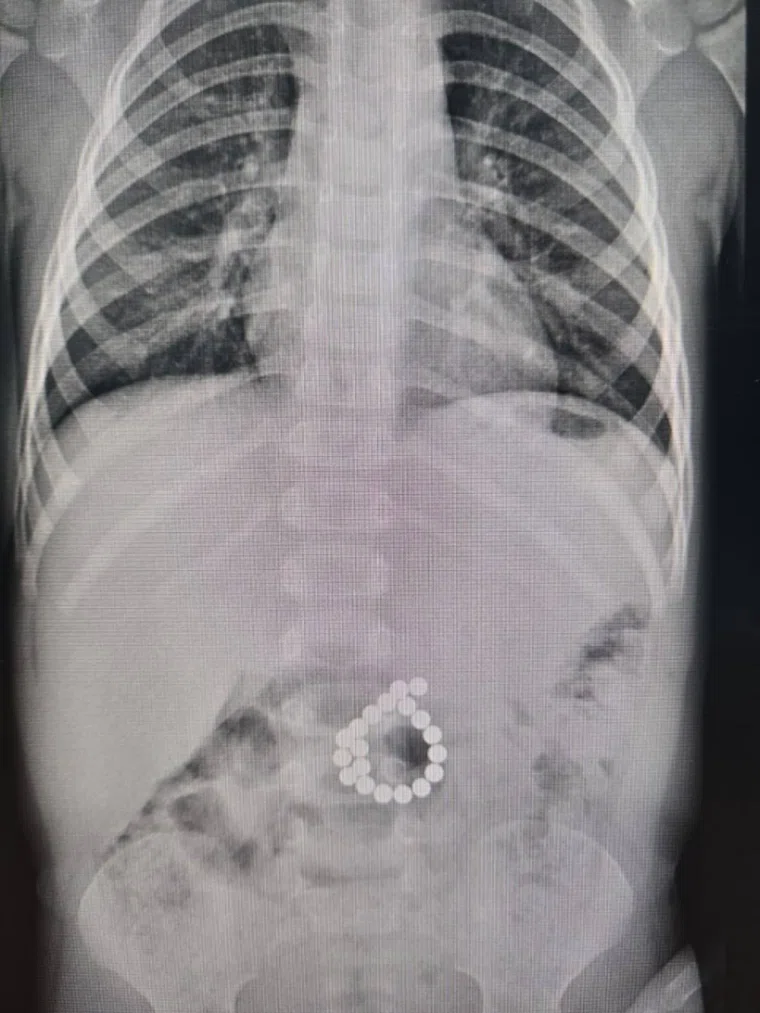

В Сургуте (ХМАО) мальчик в возрасте 2 года и 7 месяцев поступил в больницу с жалобами на сильную боль в животе и высокую температуру. Как оказалось, пару дней назад он играл с магнитным конструктором. Медики удалили из его кишечника 19 деталей.

«В Центр охраны материнства и детства поступил мальчик 2 года 7 месяцев с высокой температурой и сильными болями в животе. Выяснилось, что за несколько дней до этого он играл с магнитным конструктором и проглотил сразу несколько деталей. Во время экстренной операции в толстой кишке обнаружили 19 магнитов и двойную перфорацию», — поделился глава депздрава ХМАО Роман Паськов в telegram-канале.